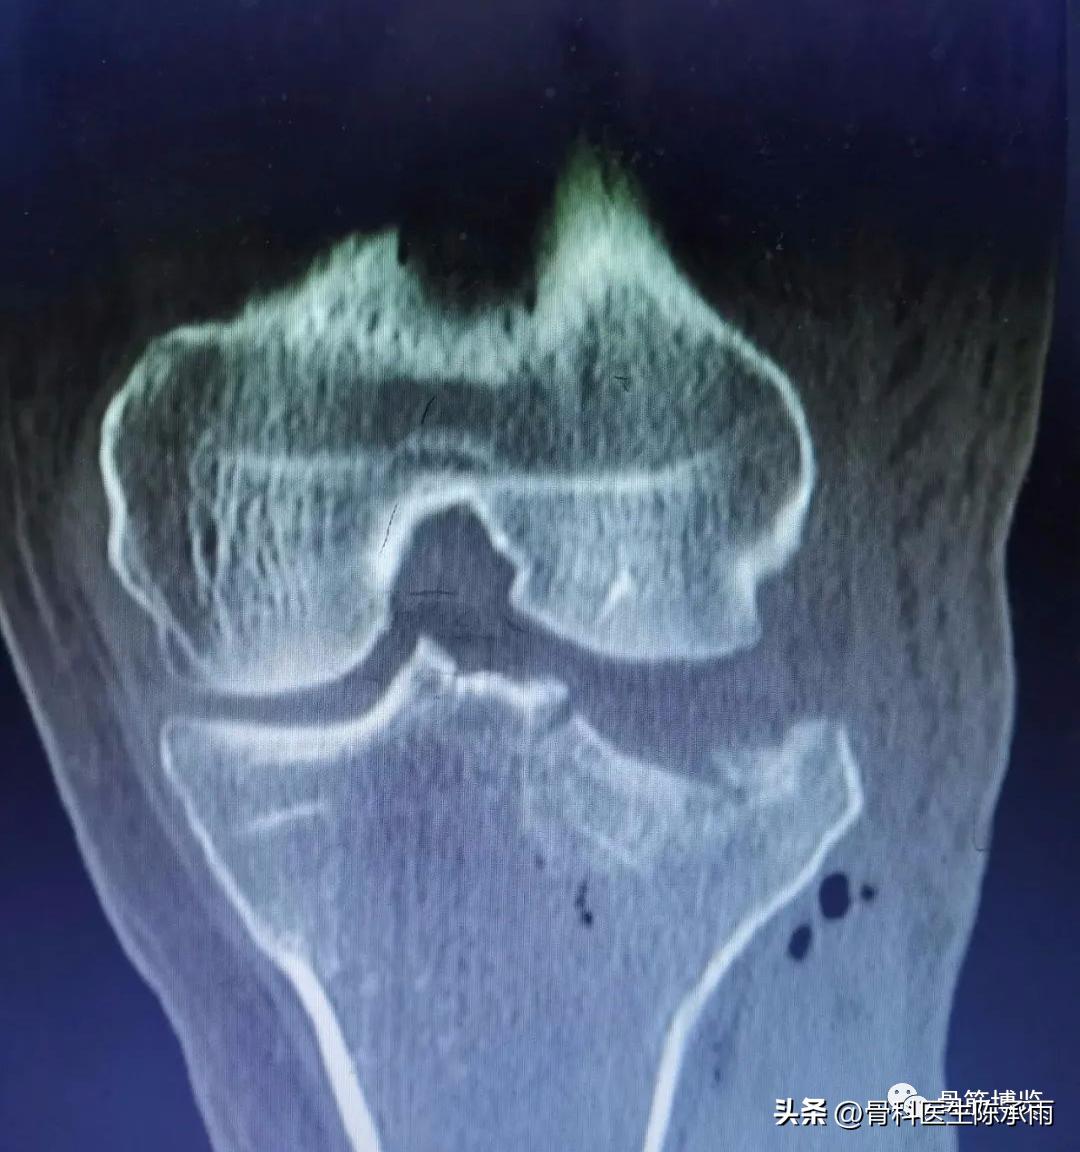

胫骨平台骨折的分型比较多,我们临床上常用的就是Schatzker分型和AO骨折的分型,还有骨折脱位的Hohi-Moore分型,这是我们常用的三个分型。

Schatzker分型来讲它一共分为六型:

一型 劈裂,

二型 劈裂塌陷,

三型 外髁的一个单纯塌陷,

四型 内髁的骨折,

五型 双髁的骨折,

六型 双髁伴干骺端的骨折,

对AO 分型来讲,现在这是AO推出来更详细的,再分为ABC。随着分型的增加,从A到C骨折的损伤程度是越来越重,治疗也越来越困难,从1到2 ,123也是这个规律,骨折的分型就是给我们表明了骨折的一个损伤的程度,治疗办法和损伤的特点。我们对于骨折脱位的分型,常用Hohi-Moore分型,这个是弥补了,Schatzker和AO分型的一些缺陷。